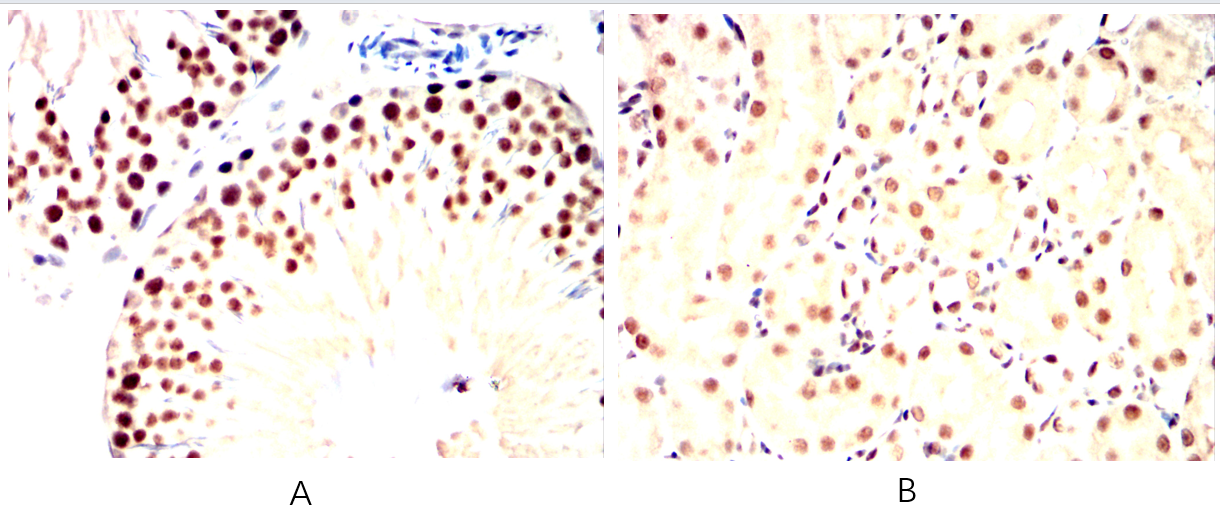

- Immunohistochemical analysis of paraffin-embedded human lung cancer tissues (left) and kidney cancer tissues (right) using SIRT1 mouse mAb with DAB staining.

- Immunohistochemical analysis of paraffin-embedded Mouse testis(A)Mouse kidney(B) using SIRT1 mouse mAb with DAB staining.

- Immunohistochemical analysis of paraffin-embedded Rat spleen(A)Rat liver(B) using SIRT1 mouse mAb with DAB staining.

- Immunohistochemical analysis of paraffin-embedded Rabbit spleen(A)Rabbit liver(B) using SIRT1 mouse mAb with DAB staining.